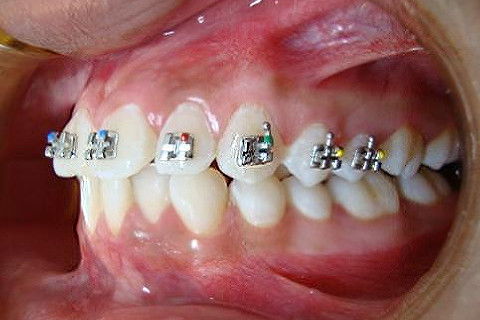

Paciente D. F. S., 19 anos, com queixa principal o apinhamento superior e inferior. Realizado o diagnóstico foi proposto duas opções de tratamento: exodontia de 04 pré-molares ou exodontia de incisivo inferior e slices superior, verticalização do molar 47 para futura instalação de implante do 46.

O tratameno foi iniciado com a montagem completa do aparelho superior e inferior, a indicação da exodontia do elemento 41, alinhamento e nivelamento.

Atualmente estamos com  04 meses de tratamento, podemos notar uma grande evolução no caso em pouco tempo.